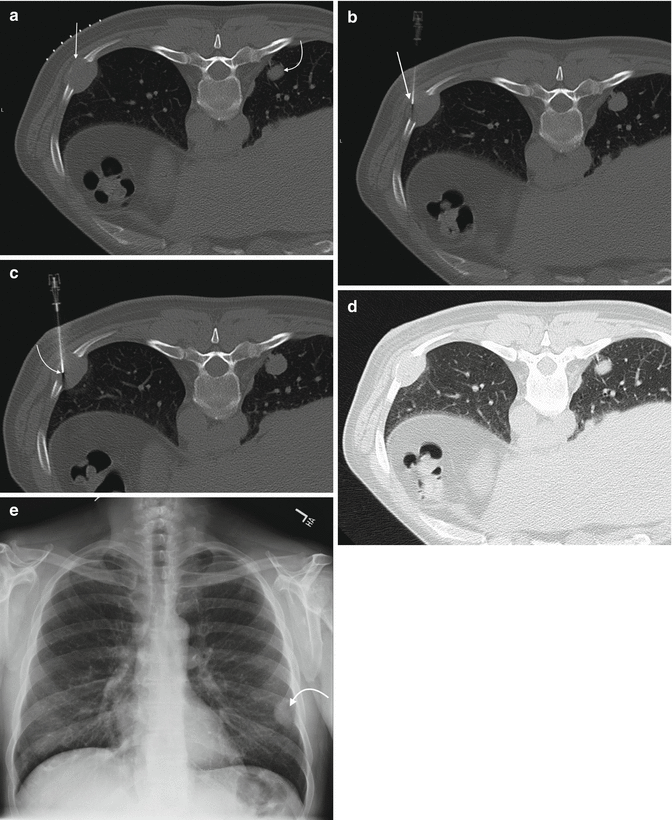

From radiologykey.com

Rib Biopsy Radiology Key Ribs Anatomy Radiology They lead to a decreased chest volume that may. Short ribs do not extend as far anteriorly as the sternum; And pseudarthrosis of the first rib. normal rib variants include cervical, intrathoracic, and pelvic ribs; The rib series is often considered to be an unnecessary, unjustified. the ribs ap view is a specific projection employed in the assessment. Ribs Anatomy Radiology.